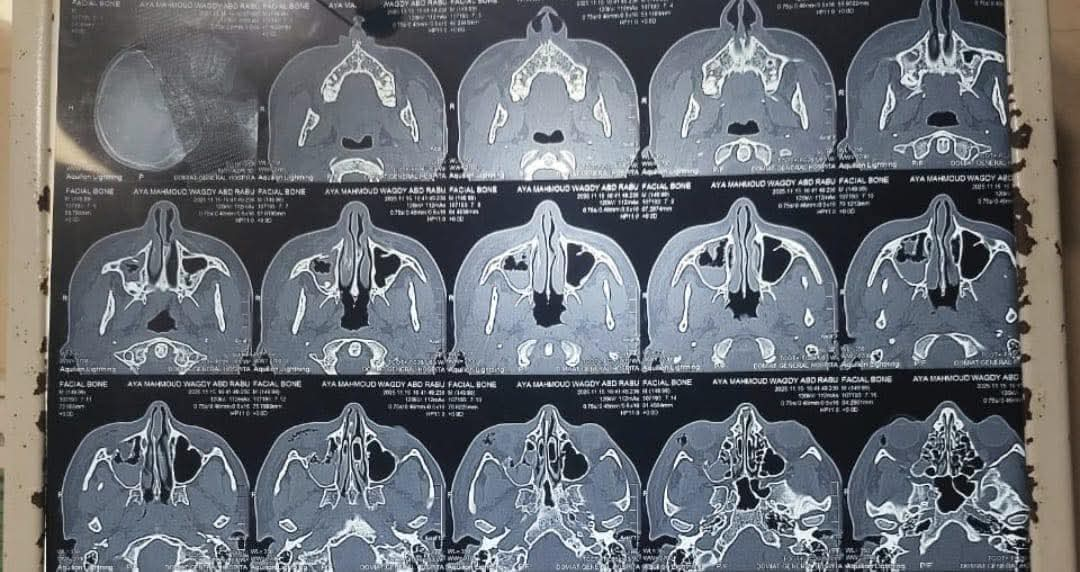

قسم الاستقبال

وكانت المريضة قد وصلت إلى قسم الاستقبال وهي تعاني من تورم شديد وألم حاد وصعوبة في حركة العين، حيث جرى تقديم الإسعافات الأولية لها بشكل عاجل، ثم حجزت بالمستشفى لاستكمال سلسلة من الفحوصات الدقيقة من إشاعات وتحاليل لتحديد طبيعة الإصابة ووضع خطة التدخل الجراحي الملائمة. وبعد استقرار علاماتها الحيوية، تم تجهيزها لدخول العمليات وفق البروتوكولات المعتمدة لضمان أعلى درجات الأمان الطبي.

ونجح فريق جراحة الوجه والفكين بالمستشفى،  في إجراء جراحة دقيقة لتثبيت الكسر باستخدام شبكة عين ومسامير طبية مخصصة، وذلك في عملية دقيقة تتطلب مهارة عالية ودقة في التعامل مع محيط العين نظرًا لحساسية المنطقة وتشابك الأعصاب والأوعية الدموية بها. وقد خرجت المريضة من العمليات بحالة جيدة وتتماثل حاليًا للشفاء داخل العناية تحت المتابعة المستمرة من الفريق الطبي.